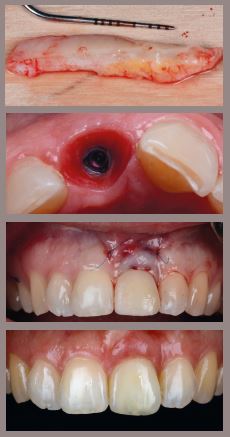

IMPLANT PROSTHETICS AND SOFT TISSUE SHAPING

- Peri-implant biology

- Bone level vs Tissue level implants?

- Importance of healing abutment design and uncovery techniques

- Evidence -based biocompatible materials in prosthetics

- Temporary solutions (immediate or delayed?)

- Screw retained vs cemented solution?

- Submergence design for tissue health

- Restoration Driven Tissue Regeneration (RDTR)

- Umbrella Concept

- Capturing submergence tissue profile for final restoration

- Digital workflow in implant prosthetics

HANDS-ON:

1. Fabrication of individual healing cap

2. Fabrication of temporary for proper tissue shaping on model

3. Critical and subcritical contour modelling